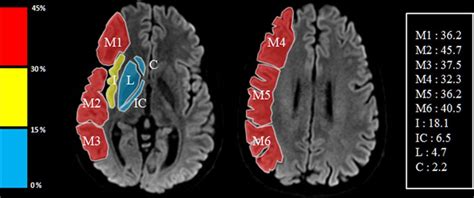

Fig. 3.2, [ASPECTS (Alberta Stroke Programme Early...]. Diseases of